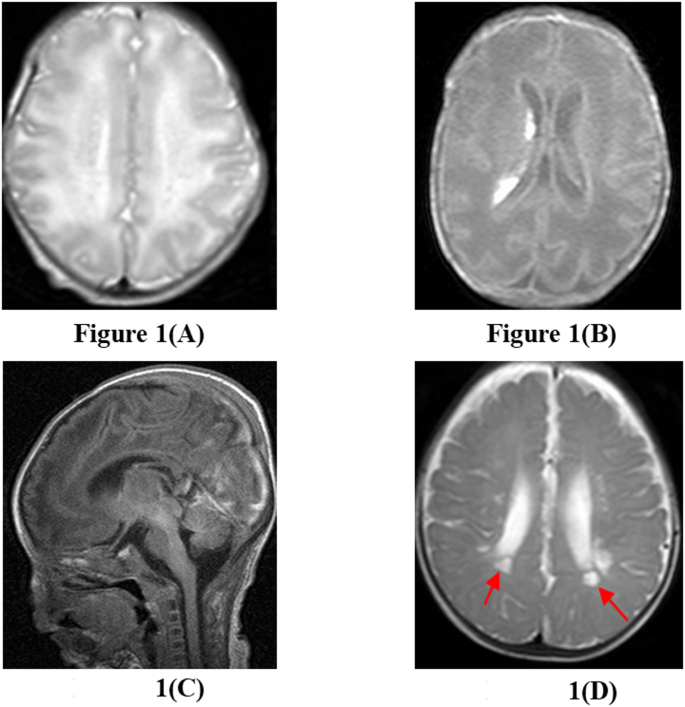

MRI findings of the 43 neonates with brain injury at their term-aquivalent age were as follows: white matter injury in 17 cases, intraventricular/periventricular/subarachnoid hemorrhage in 19 cases, and grey matter injury in 7 cases. Figure 1 represents examples of different brain injuries identified in MRI scans.